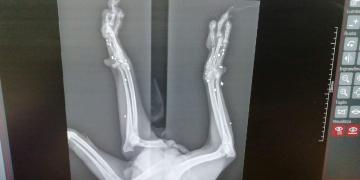

LIBERO Era solo un cucciolo….!!! Gli avevano sparato!! Fu trovato sofferente che zoppicava, nella periferia di Palermo, laddove abbandonano i cani non desiderati. FORSE LIBERO ERA RIUSCITO A SCAPPARE PRIMA CHE IL SUO CARNEFICE LO FINESSE Qualcuno si era divertito a sparare alle sue zampette.. Un cucciolo … come si puo’ fare questo ad un esserino innocente?

Adesso Libero si trova ancora in Sicilia in provincia di Palermo. Sono già passati 5 anni e per lui nessuno ha mai chiamato.. RIPROVIAMOCI.. Libero ha una zampetta impallinata che ha frantumato le ossa. Purtroppo non si puo’ intervenire chirurgicamente e cio’ gli impedisce di poggiarla in terra, ma questo non fa di lui un cane non autosufficiente. Libero è un cane dolcissimo di taglia medio piccola, bellissimo, timido con gli altri cani e si sottomette a loro,povero tesoro. Corre e gioca normalmente. Castrato e vaccinato e soprattutto negativo alla Leishmania.